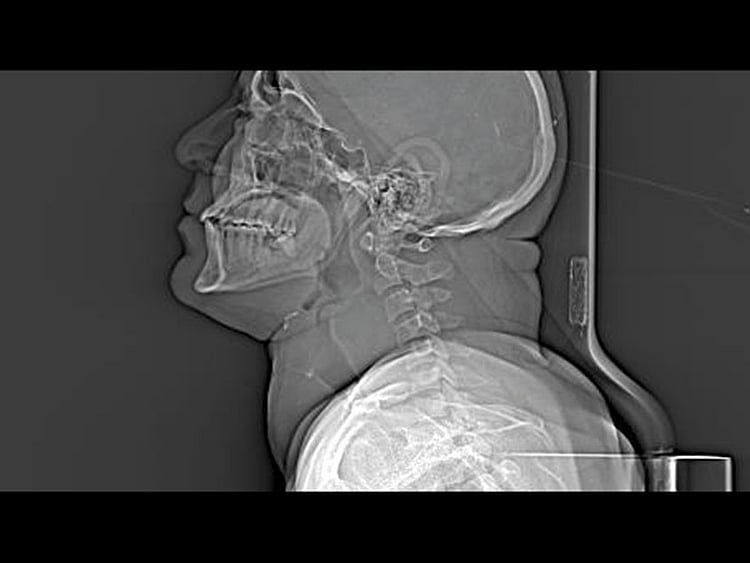

Dubai: In a rare surgery lasting five hours, doctors excised a thyroid gland weighing 550 gms from the neck of a 46-year-old expatriate.

This butterfly-shaped gland in our throat normally weighs about 15-25 gm.

“Clinical examination of the patient indicated that his colloid goitre had grown into a mass measuring 18 x 16cm involving most of the neck down to the anterior border,” Dr Goel said.

“Excision of the entire gland was challenging as the mass growing on it was affecting the vital carotid artery and internal jugular vein as also compressing the trachea,” said Dr Rahul Tugnait, specialist in General Surgery at the hospital. “The trachea is made of soft cartilage and there was danger of slicing through it.” Any mistake could rupture either the carotid artery or jugular vein or cause respiratory distress to the patient.